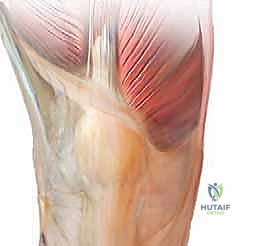

1. الوصول الجراحي والتقييم الأولي

يتم إجراء شق جراحي أمامي دقيق، مع الحفاظ على الأنسجة العضلية قدر الإمكان لتسريع التعافي. يتم كشف المفصل التالف وتقييم حجم الضرر في الغضاريف والزوائد العظمية.